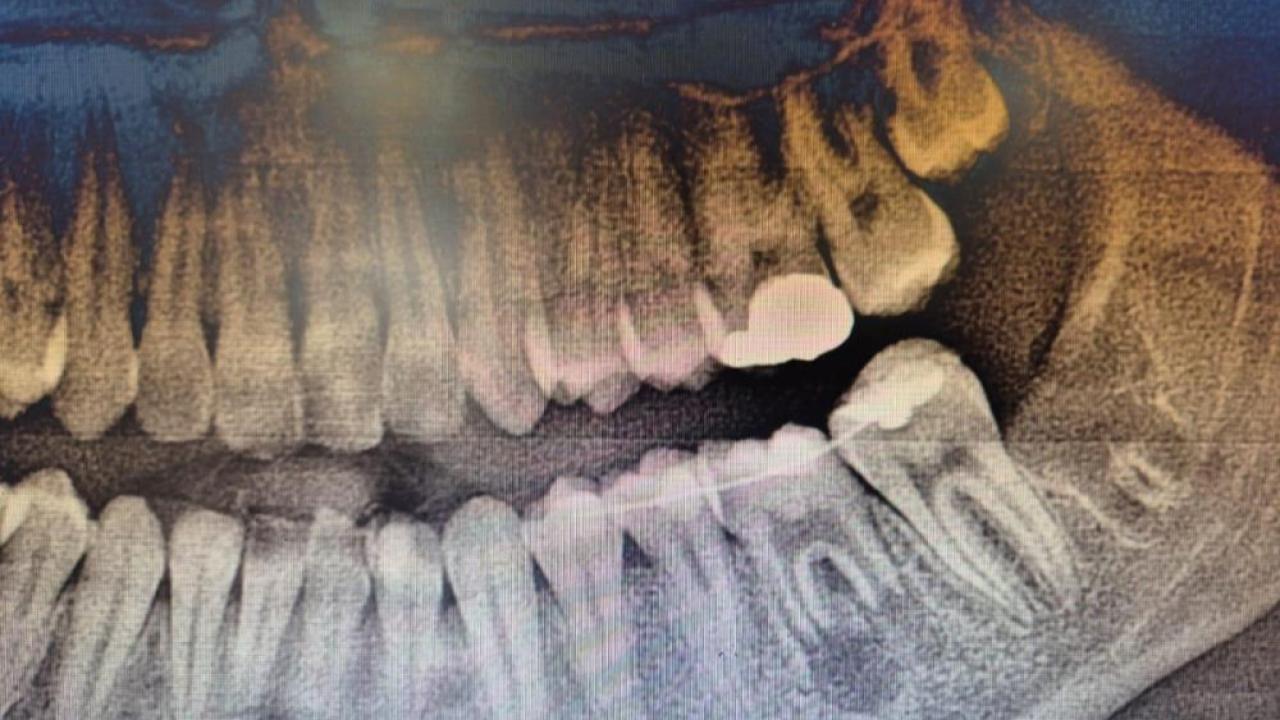

İleri düzey çürük nedeniyle daimi azı dişi çekilen hastaya, yaşı gereği çene gelişimi devam ettiği için klasik implant tedavisi uygun görülmedi. Bunun yerine, hastanın ağzında gömülü halde bulunan yirmi yaş dişi, uzman ekip tarafından cerrahi operasyonla çıkarılarak çekilen dişin yerine nakledildi.

Operasyon sırasında, dişin sağlıklı bir şekilde tutunmasını sağlamak için hastanın kendi kanından elde edilen PRF (Platelet Rich Fibrin) materyali, nakil öncesi hazırlanan diş yuvasına yerleştirildi. Bu uygulama, doku iyileşmesini hızlandıran ve hücre yenilenmesini destekleyen doğal bir yöntem olarak öne çıkıyor. Bu tedavi yöntemi, hastanın kendi dişi kullanıldığı için doğal görünüm, uyum ve fonksiyon açısından büyük avantaj sağlıyor. Aynı zamanda, vücut tarafından kabul edilme oranı yüksek olduğundan, uzun vadeli başarı şansı da oldukça yüksek.

Uzmanlar, diş ototransplantasyonunun, uygun şartlar oluştuğunda özellikle çocuk ve genç hastalarda diş kayıplarına karşı etkili ve güvenilir bir alternatif olduğunu vurguladı.